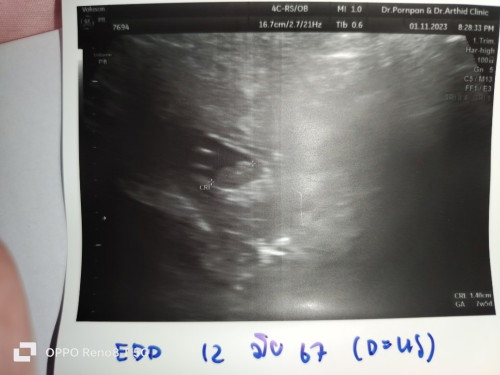

หลังจากน้องเสียในท้อง 34+5 สัปดาห์

น้องเสียในครรภ์เนื่องจากน้ำคร่ำแห้ง ตอน 34+5 20มิ.ย66 ตอนนี้น้องกลับมาแล้วค่ะ 2 เดือนแล้ว